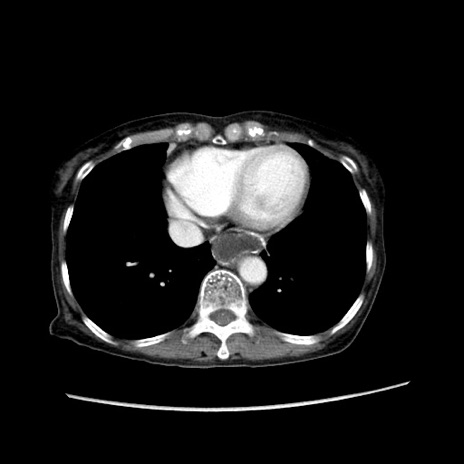

症例25(横断像)

【症例】80歳代女性

【主訴】胸のつかえ感

【現病歴】約9時間前に食後から胸のつかえた感じあり、嘔吐あり、来院。

【既往歴】胃癌(全摘)、胆摘、虫垂炎

【身体所見】心窩部に圧痛あり、反跳痛なし。

【データ】WBC 5700、CRP 0.05